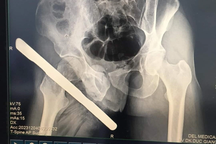

Bệnh nhân được thăm khám (Ảnh: Bệnh viện cung cấp).